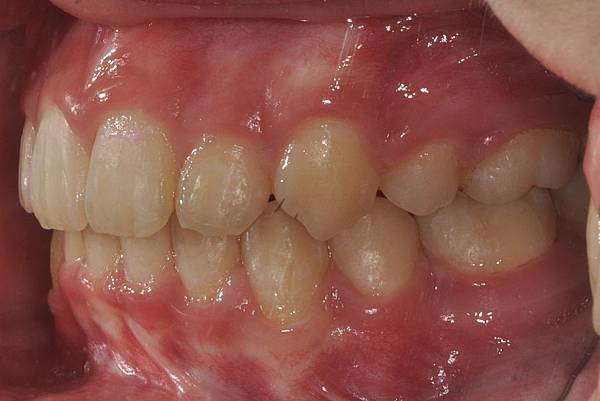

拔牙改善高位虎牙

虎牙妹的女神蛻變之旅~

此案例因為空間不足排列牙齒,

考量到不拔牙將使得牙齒前凸破壞患者原本和諧的側臉。

故上下左右各拔一小臼齒。

治療前/治療後

-以上案例由林昇進醫師提供